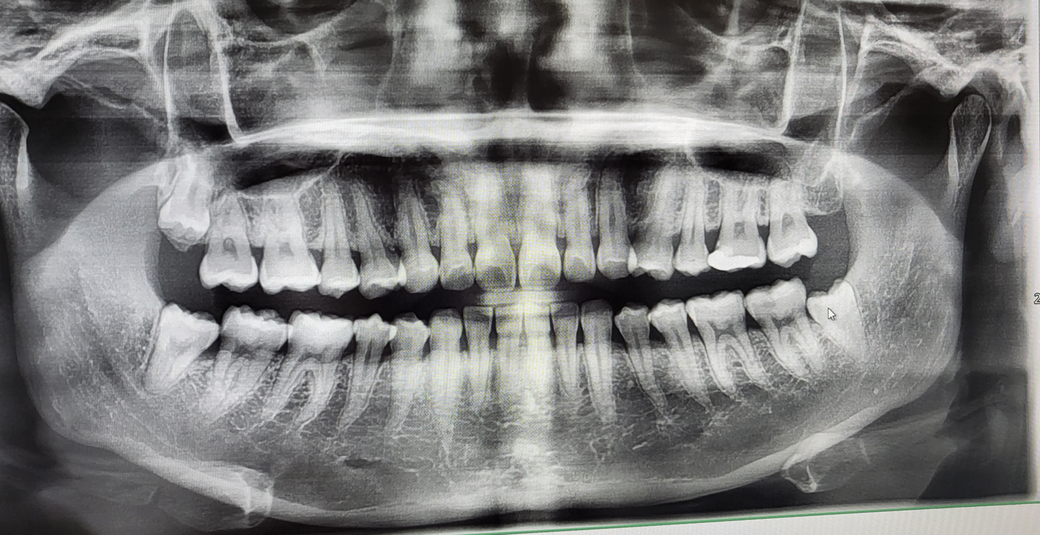

예방법이나 다른 방법이 없는지요... 사진은 사랑니 발치 전 사진입니다 (오른쪽 아래 사랑니 발치하였습니다)

사진상에서 이미 사랑니 발치전에 사랑니 바로옆 어금니 뒷쪽의 충치가 있는 상태입니다. 그리고 어금니의 잇몸뼈도 이미 내려가 있는 상태입니다. 이와같이 사랑니가 매복되면 사랑니 바로옆 어금에 손상이 올 수 밖에 없습니다. 그래서 사랑니를 가능한 빨리 빼라고 하는 것입니다. 치주염이라고 질문하신 것은 어금니 치주염을 이야기 하는 것으로 보이며 치은절제술 또는 치은박리술 등등을 할 수 있습니다. 어느 것을 하더라도 예후는 좋지 않을 수 있습니다.

파노라마 사진상으로 보면 사랑니 발치시 크게 어려움이 잇거나 하진 않을껏같은데요. 사랑니 발치를 하고 그쪽에 치주염이 발생하는경우는 흔치 않습니다. 혹시 다른곳에 문제가 잇을수도 잇으니 대학병원 치주과를 가셔서 검진을 받아보시는게 좋을것같습니다. 염증이 잇다면 염증을 제거하고 소독을 해줘야됩니다.